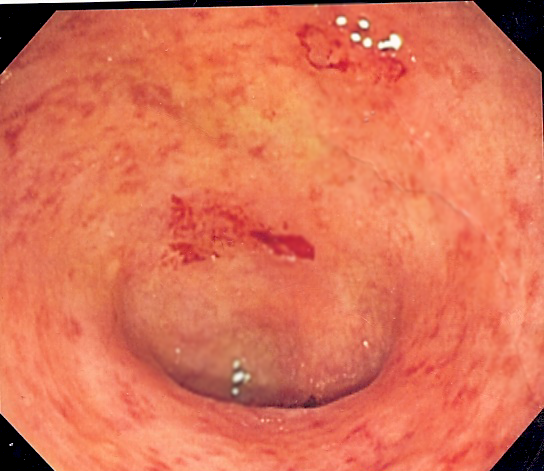

Ulcerative colitis is a condition that results in inflammation and sores called ulcers in the lining of your large intestine as well as your sigmoid colon and rectum. Ulcerative colitis has been confused with Chron’s disease, however, Chron’s disease can develop anywhere in your digestive tract and usually affects multiple separate areas while ulcerative colitis affects a single continuous piece of your large intestine. Ulcerative colitis also affects only the inner lining of your large intestine while Chron’s disease can penetrate deeper in the tissue. Te exact cause of ulcerative colitis remains unknown, however, researchers do know that it is not caused by stress though stress can aggravate your symptoms. Most researchers are in agreement that the immune system is involved. It is believed there is an abnormal activation of the immune system. The immune system is comprised of cells and proteins that are responsible for protecting your body from pathogens. Because inflammation is a crucial part of that mechanism an abnormal activation of this process can lead to multiple problems. In ulcerative colitis the immune system becomes chronically activated leading to chronic inflammation. Since the majority of your immune system is in your digestive tract it is not uncommon for those areas to be significantly impacted. Many researchers also believe that genetics is what makes you susceptible to an abnormal activation of your immune system. Many people with ulcerative colitis as well as other types of inflammatory bowel disease have relatives that also have some form of inflammatory bowel disease. Many of those are first degree relatives like brothers or sisters that also have some form of inflammatory bowel disease. so far researchers have discovered around 30 different gens that may be associated with ulcerative colitis including the immuglobulin receptor gene as well as areas on certain genes. The research is in it’s early stages but, confident the information obtained so far will help them in not only understanding the disease but treating it.

The symptoms of ulcerative colitis vary from person to person depending on the extent of the disease. People whose ulcerative colitis affects only the sigmoid colon next to the rectum tend to have milder symptoms than people whose ulcerative colitis affects the large intestine. Ulcerative colitis is classified into types, the type of ulcerative colitis you have is determined by where it is located and how extensive the inflammation is. Each type has it’s own set of symptoms. In proctosigmoiditis, which affects the sigmoid colon and rectum, you would experience rectal bleeding and a feeling of urgency as well as feeling like you need to have a bowel movement when your colon is empty. Some people with this type also develop abdominal cramps and bloody diarrhea. If the inflammation is only in your rectum it’s called ulcerative proctitis and with this type you would experience mild rectal bleeding that comes and goes which in most cases is the only symptom of this type. However, if the inflammation is severe you may also experience rectal pain as well as urgency and the need to have a bowel movement even though your colon is empty. In left sided colitis, the inflammation begins at your rectum and continues up the left side of your colon you would experience abdominal cramps especially on the left side and bloody diarrhea as well as weight loss. When your entire colon is affected it’s called universal colitis. If you have this type of ulcerative colitis you would experience abdominal pain and cramping as well as bloody diarrhea along with fever and night sweats, fever, and weight loss. This type is more severe and more difficult to treat. There is also a rare form of universal colitis that is very severe, people with this type are extremely ill. They usually suffer from dehydration due to severe protracted diarrhea, they also have more severe abdominal pain and are at risk for developing complications.